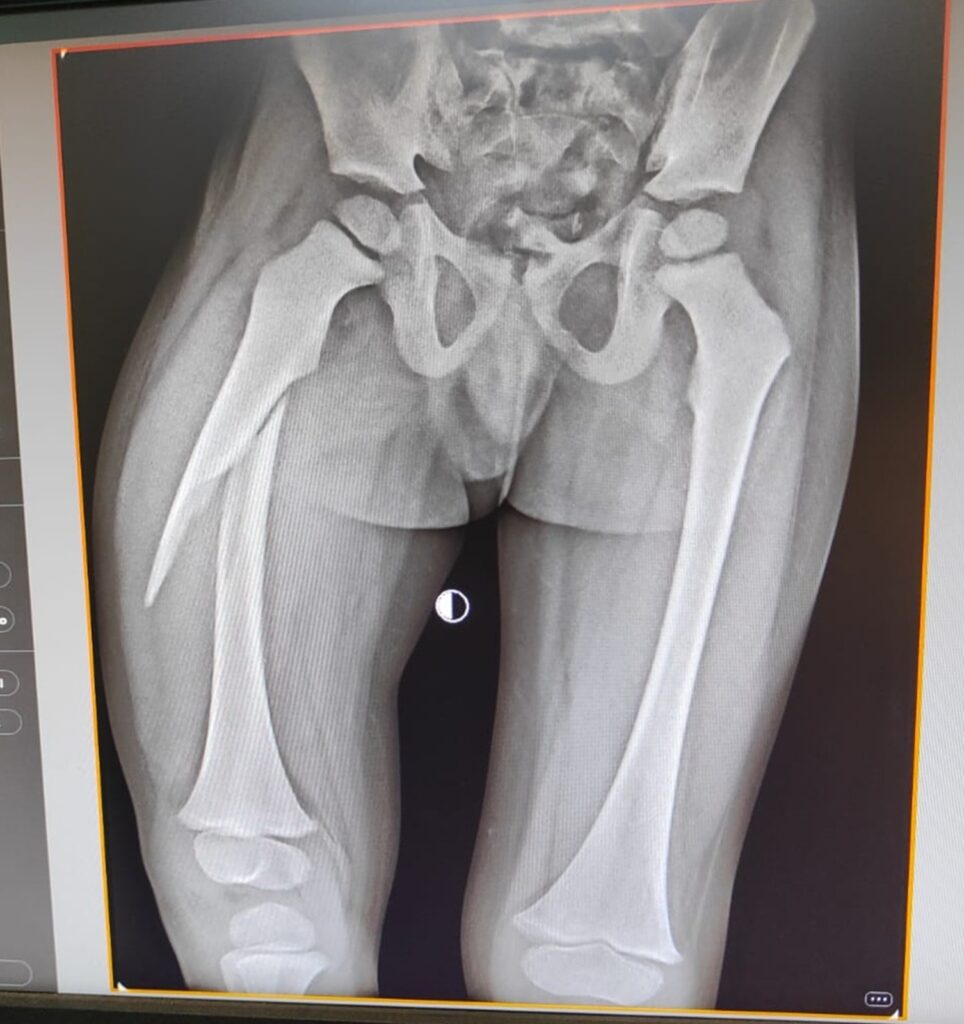

बेमेतरा,12 सितम्बर । शहर के प्राइवेट आयुष्मान अस्पताल में इलाज में लापरवाही का मामला सामने आया है। यहां उपचार के बाद चार साल के बच्चे का पैर छोटा हो गया है। बच्चे की 9 माह पहले यानि नवंबर 2024 में जांघ की हड्डी टूट गई थी। जिसे आयुष्मान अस्पताल बेमेतरा में भर्ती कराया गया था। उपचार के बाद आज के समय में बच्चे सीधे खड़ा नहीं हो पा रहा है। क्योंकि, उसका एक पैर छोटा हो गया है। पीड़ित पिता ने स्वास्थ्य विभाग में लिखित में शिकायत दर्ज कराई है। ग्राम कठिया निवासी प्रहलाद साहू ने बताया कि 18 नवंबर 2024 को चार वर्षीय पुत्र सिद्धार्थ साहू का खेलने के दौरान जांघ की हड्डी (फीमर) टूट गया था। आयुष्मान अस्पताल बेमेतरा में भर्ती कराया,जहां इलाज के बाद बच्चे का पैर छोटा हो गया है। क्योंकि, इलाज में गंभीर लापरवाही बरती गई है। टूटी हुई हड्डी सही तरीके से नहीं मिल पाया। इस लापरवाही के कारण मासूम का एक पैर दूसरे पैर से छोटा हो गया है,जिससे उसे चलने परेशानी हो रही। इतनी कम उम्र में शरीर में असमानता आ गई है, जो भविष्य में उनके जीवन पर गंभीर प्रभाव डाल सकती है। पिता प्रहलाद साहू ने लापरवाही का आरोप लगाते हुए जांच कर डॉक्टर के खिलाफ कार्रवाई की मांग किया है। उन्होंने बताया कि आयुष्मान अस्पताल में हड्डी रोग विशेषज्ञ डॉ.अंकुर कुंडू ने ही प्लॉस्टर किया था।

इस मामले में आयुष्मान अस्पताल बेमेतरा के संचालक डॉ.अनिल पटेल ने अपना पक्ष रखा है। उन्होंने कहा कि बच्चे का पैर टूटने के बाद केवल प्लास्टर लगाया गया है। किसी भी प्रकार का कोई ऑपरेशन नहीं किया हुआ है। बच्चे की हड्डी 90 प्रतिशत सीधा है। आने वाले दिनों में वह पूरी तरह से ठीक हो जाएगा। वहीं, डॉ.अंकुर कुंडू ने कहा कि जैसे-जैसे बच्चा बड़ा होगा दोनों पैर बराबर हो जाएगा।